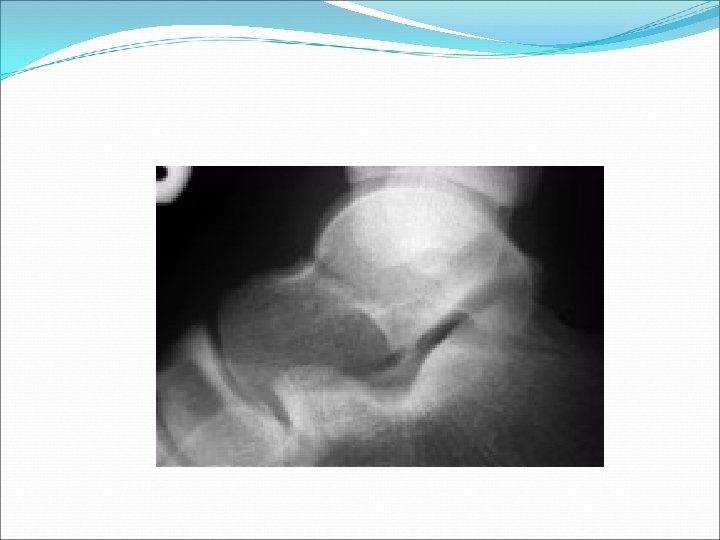

Talar Neck #

R calcaneus x-ray: